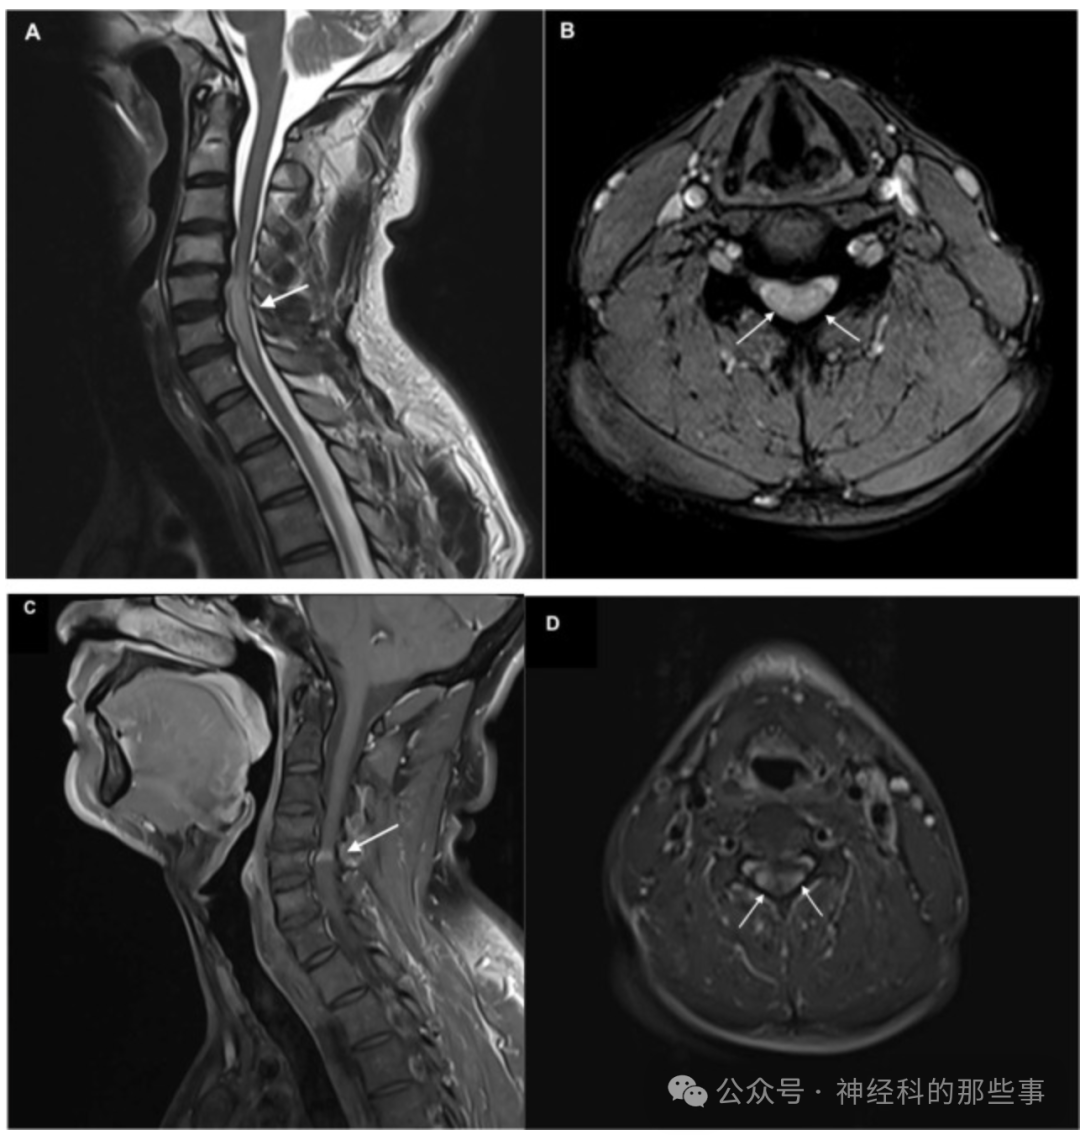

pancake征(煎饼征)图颈椎病患者脊髓MR(A) 矢状位MRI显示颈椎病伴脊髓压迫,最严重狭窄位于C4-C5。 (B) 横轴位ERGE图像显示同一水平的环状T2高信号。 (C) 在C4-C5的对比增强图像上有一个类似煎饼的增强信号。 (D) 对比增强的T1 FS图像显示增强主要位于脊髓的外侧部分。